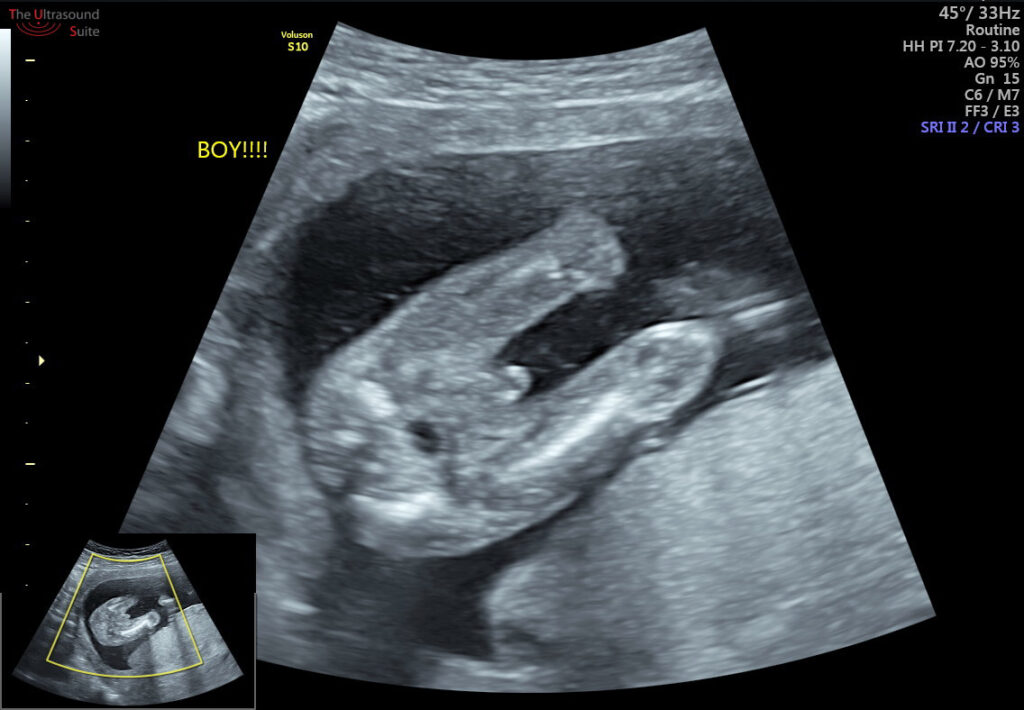

Gender Determination

While the primary purpose of the anomaly scan is to assess the baby’s health and development, some parents may also choose to find out the baby’s gender during this scan. However, it is important to note that not all healthcare providers offer gender determination during the anomaly scan, and it may not always be possible to accurately determine the baby’s gender.